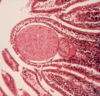

Rabbit Coccidiosis biliary hyperplasia

Larger→ oocysts –elongated

Smaller → gamont– circular

Billiary cysts in the bile duct

Eimeria stiedai

Rabbit Coccidiosis biliary hyperplasia

Circular gamonts sourounded by white layer

Eimeria stiedai

Rabbit Coccidiosis biliary hyperplasia

Circular gamonts sourounded by white layer

Eimeria stiedai